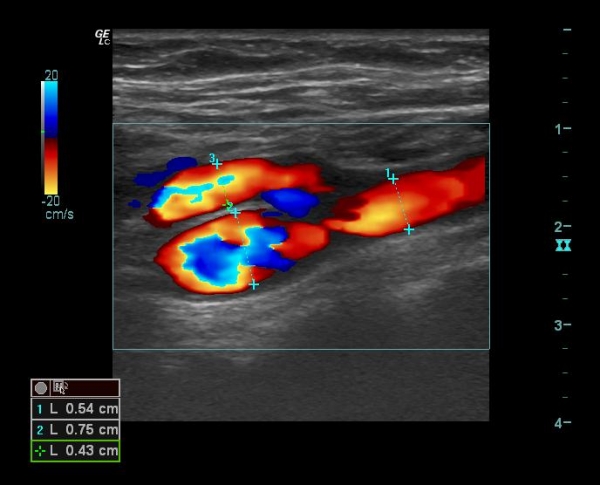

Случай №2 (мужчина)

Из картинок видно, что соотношение ВСА/НСА у мужчин ближе к 1, у женщин >1

То есть относительно притока к головному мозгу, у женщин возможности выше, чем у мужчин. Отсюда выводы? (вопрос 3). Подумаем. Потом обсудим, как интерпретирует Оксфорд.